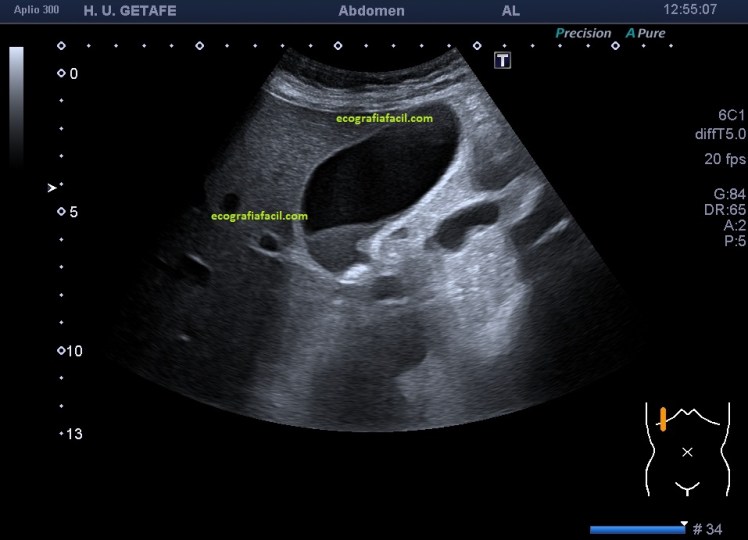

Finalmente, la imagen 4, donde encontramos una vesícula sin barro biliar y con una gran colelitiasis que provoca una evidente sombra acústica posterior. La vesícula es anecoica, sin presencia de barro, el paciente puede ser completamente asintomático y no saber que esa ecoestructura, redondeada, hiperecogénica causante de sombra acústica posterior y móvil, que así suelen ser las colelitiasis, se alberga en el interior de su vesícula. Las colelitiasis suelen ser variable en número, tamaño e incluso forma.